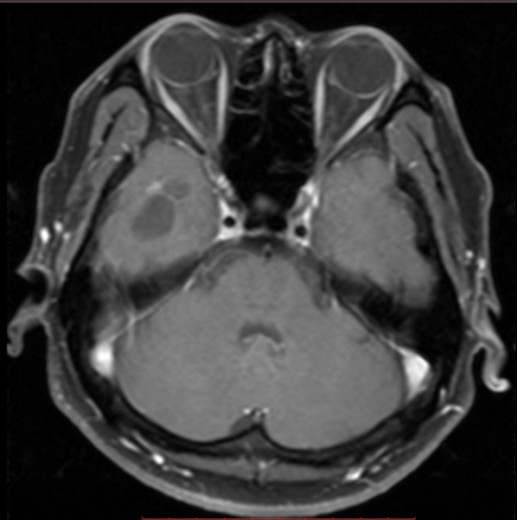

图3. 头颅MRI提示右侧颞极囊状病灶,周围异常信号。

图4. 头颅增强MRI提示右侧颞极囊状病灶周边点状增强。